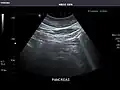

Pancreas: Visualized portions unremarkable.

Pancreas